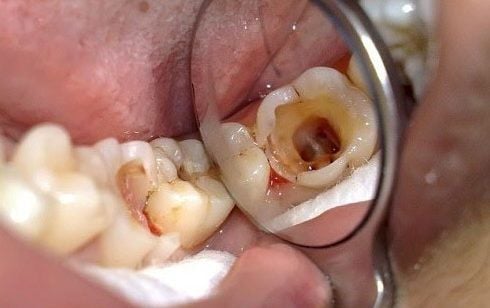

Răng bị sâu: Các lỗ sâu li ti hoặc sâu men răng cần được làm sạch và lấp đầy.

Làm sạch vết sâu: Sử dụng dụng cụ chuyên dụng để loại bỏ hoàn toàn mô răng sâu (nếu có), ngăn chặn vi khuẩn tái phát.

Tiến hành trám Composite: Bác sĩ đưa vật liệu Composite lên răng, tạo hình tỉ mỉ sao cho khớp với hình dáng răng thật. Sau đó dùng đèn Halogen/LED để làm đông cứng vật liệu.